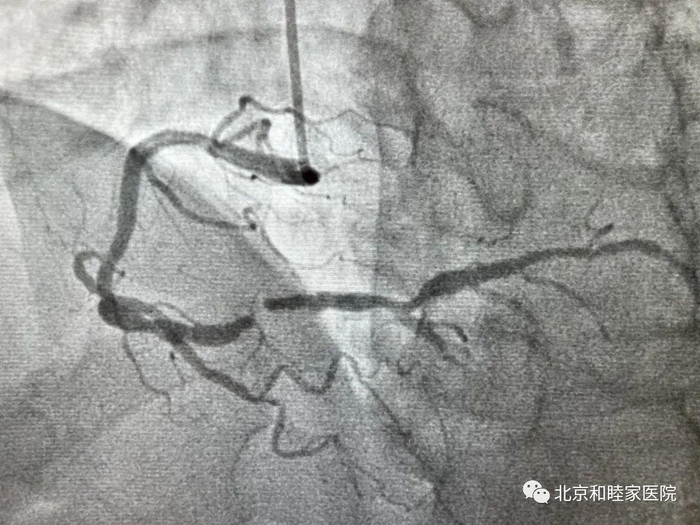

5 月 10 日,北京和睦家医院心脏中心成功为一位 68 岁男性患者植入 1 枚美敦力第四代 Resolute OnyxTM 药物涂层支架。据美敦力公司反馈,这是该产品在中国大陆第一例由非公立医院完成的手术。

该患者是一位 68 岁的男性,有高血压、糖尿病、高血脂、肾功能不全、前列腺癌病史,2 年前因为心绞痛、右冠状动脉严重狭窄植入 1 枚支架,近 10 天出现劳力性心绞痛。

复查冠脉造影后提示:右冠状动脉近段原支架通畅,中段严重狭窄 99%。

手术过程非常顺利,在 OCT 的指导下,支架准确覆盖了病变且贴壁良好。在这种治疗方案下,患者经过 1 个月的双联抗血小板之后,就可以进行前列腺的外科手术了。